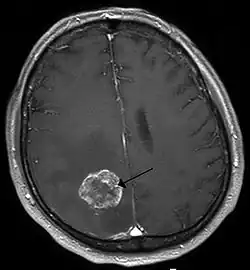

Brain imaging (neuroimaging such as CT or MRI) is needed to determine the presence of brain metastases.[6] In particular, contrast-enhanced MRI is the best method of diagnosing brain metastases, although primary detection may be done using CT.[10] Positron emission tomography (PET) is usually not considered suitable for imaging of brain metastases, because the most frequently used PET-radiotracer, 18F-FDG, does not only accumulate in the tumor but is naturally taken up by normal brain tissue, usually resulting in insufficient tumor-to-background contrast. PET-imaging of brain metastases is however feasible using alternative radiotracers, such as the Gallium-68 labeled peptide 68Ga-Trivehexin,[13] a tracer targeting the tumor cell surface protein αvβ6-integrin. 68Ga-Trivehexin demonstrated high uptake in a brain metastasis of tonsil carcinoma but no uptake in the surrounding healthy brain tissue, enabling a delineation of the brain metastasis (see image).[14]

In the setting of brain metastasis due to malignant melanoma, MRI imaging showed high T1 and low T2 intensity due to the deposition of melanin in the brain. In susceptibility weighted imaging (SWI), it usually shows abnormal SWI hypointensity in larger proportion than brain metastasis caused by breast carcinoma.[15]